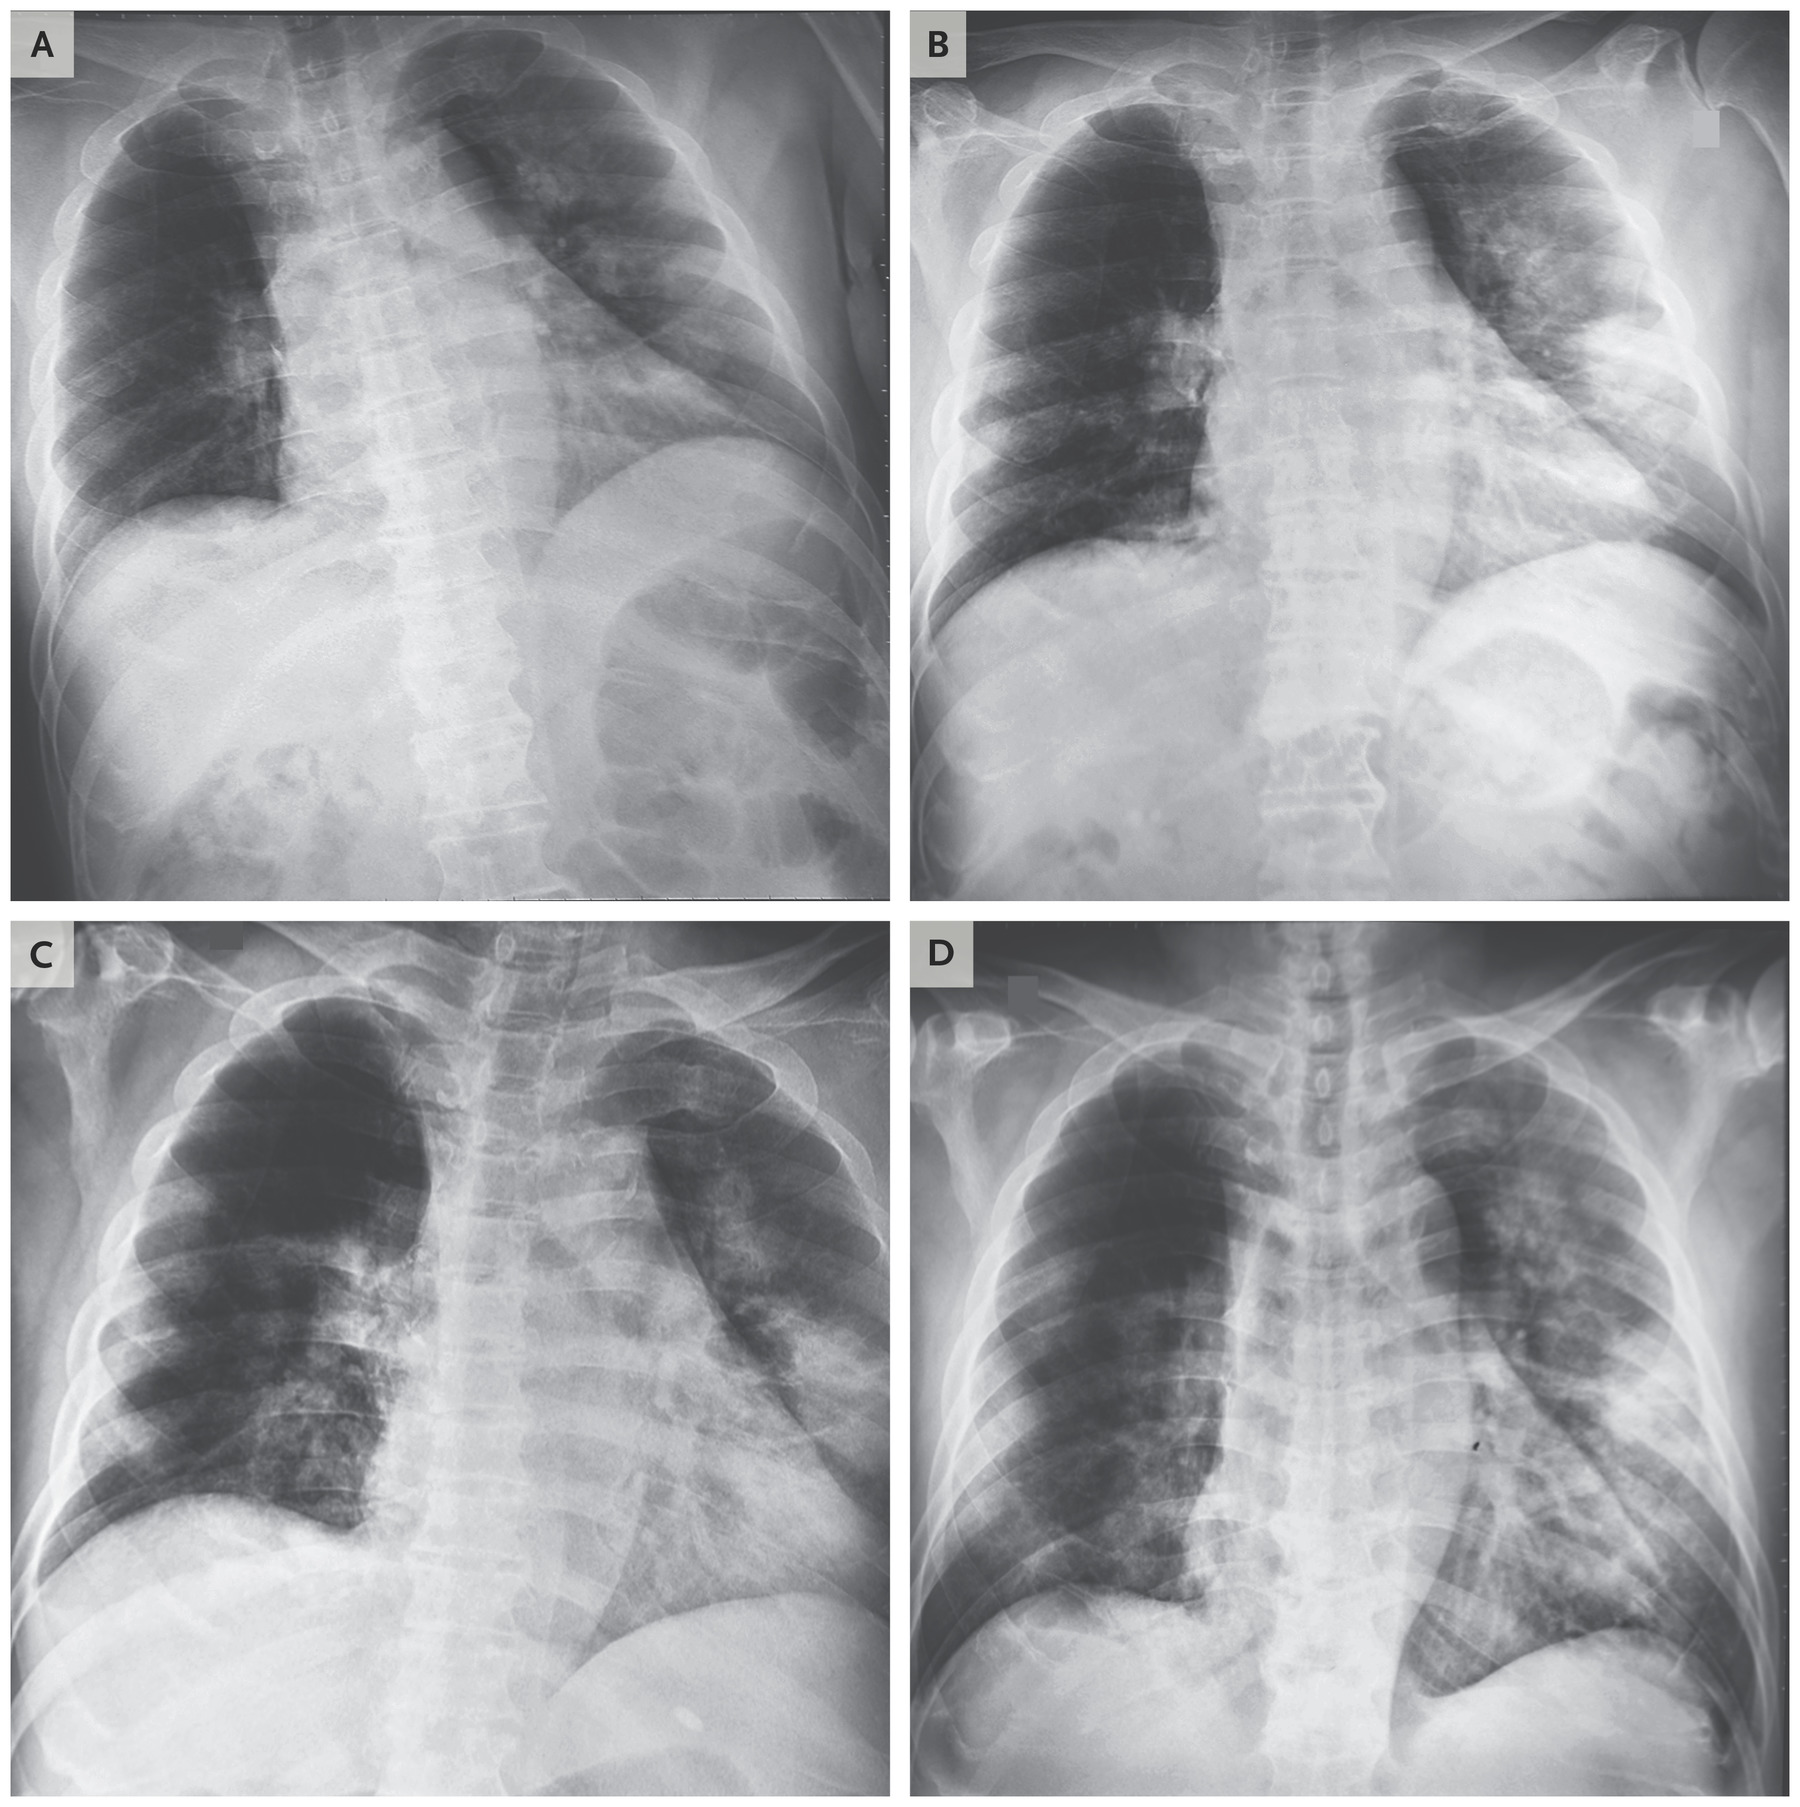

Поражение легких является одним из основных симптомов коронавируса (COVID-19). В данной статье представлены фото рентгеновских снимков, которые позволяют визуально оценить состояние легких при этом заболевании.

На фотографиях рентгеновских снимков видно, как вирус воздействует на легочную ткань. Характерные признаки поражения легких включают пятна, инфильтраты и наличие жидкости внутри легочных альвеол.

Фото рентгеновских снимков помогают врачам и специалистам визуально определить степень поражения легких и принять соответствующие меры лечения и поддержки пациента.